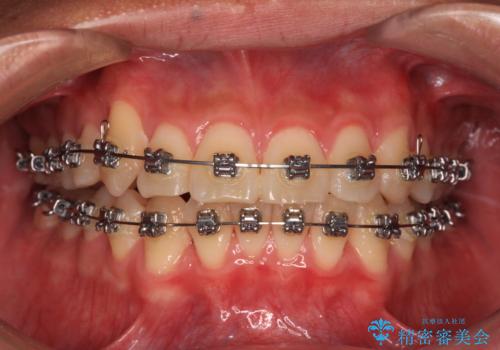

- 矯正装置

- メタルブラケット

マウスピース矯正とワイヤー矯正で悩んでいらっしゃいましたが、非常に強い咬合力であることや、お仕事柄不規則な生活リズムになることが多いとのことで、ワイヤー装置にて矯正治療を行うこととしました。